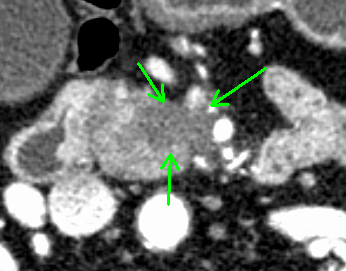

術前シミュレーション画像(CT画像)

術前の検討